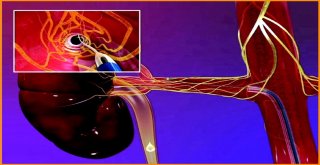

Saç Ekim Merkezi Direktörü Gülgör: Saçlarda Azalma Varsa Sebebi Azalan Testosteron Seviyesi Olabilir

Saç Ekim Merkezi Direktörü Gülgör: Saçlarda Azalma Varsa Sebebi Azalan Testosteron Seviyesi Olabilir